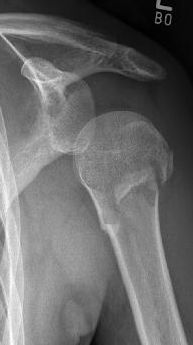

Picture: The subcapital humeral fracture shown here in the axis is not broken and only slightly bruised, so that a conservative therapy is possible. The left image shows the follow-up after 3 weeks. The patient has already started physiotherapy. The x-ray shows an increase bone healing.